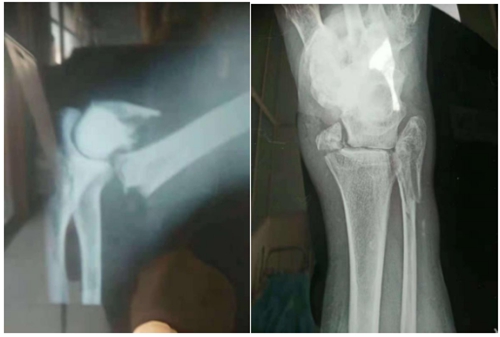

今年49岁的李师傅, 出门干活不小心摔倒导致骨折在本卫生室经中医手法复位、外敷祖传接骨膏药 1个月的治疗后,他的症状明显缓解,现已康复